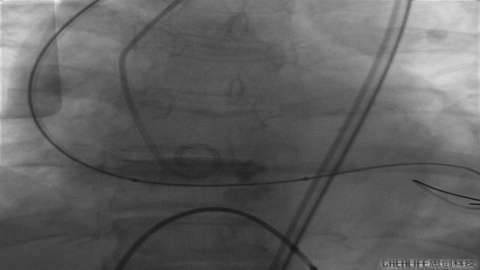

更换VenusA26号瓣膜前1/3

VenusA26号完全释放